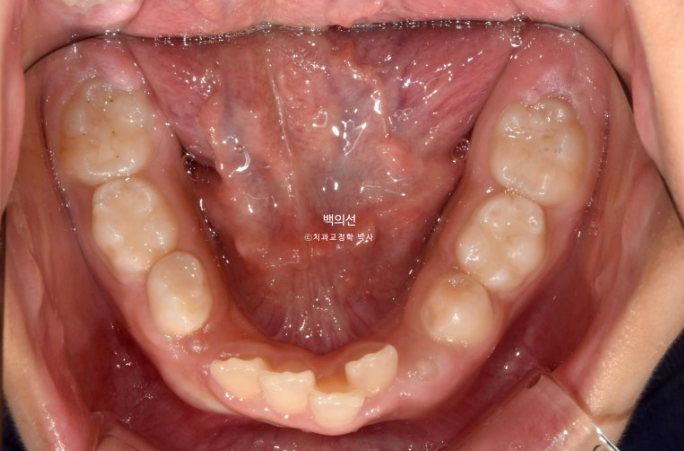

아래도 마찬가지로 악궁확장이 필요합니다.

이 날 공간이 부족하여 앞니가 삐뚤게 나왔고 곧 나올 송곳니는 공간이 부족하여 덧니로 나올 상황입니다.

삐뚤했던 아래 앞니는 가지런해졌고 송곳니는 악궁확장을 통해 공간이 생기면서 제자리로 잘 올라오게 되었습니다.

9개월 후 모습을 보면 송곳니와 작은어금니들이 많이 올라온 게 보입니다.

이제 남아있는 유치는 없고 모든 영구치가 제자리에 예쁘게 나왔습니다.

물샐틈 없는 1급 교합관계를 보입니다.